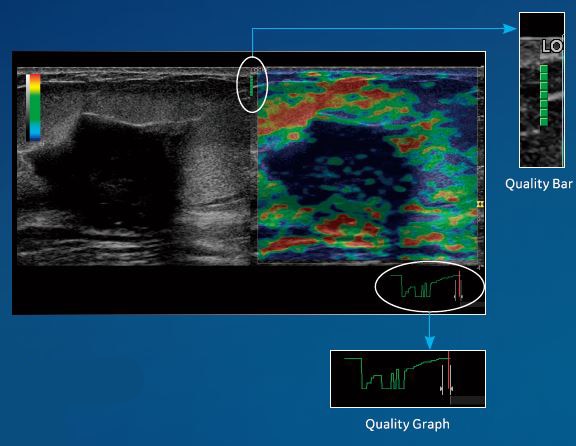

Strain Elastography

歪みの程度をカラー表示。

クオリティを示すグラフとバーで高い再現性を担保できます。